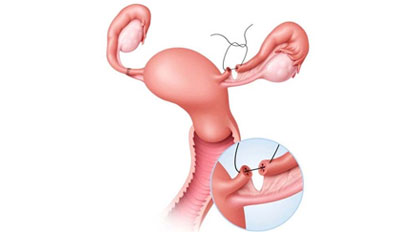

Fallopian Tube Recanalization

Fallopian Tube Recanalization (FTR) is a minimally invasive, image-guided procedure aimed at restoring patency in blocked...